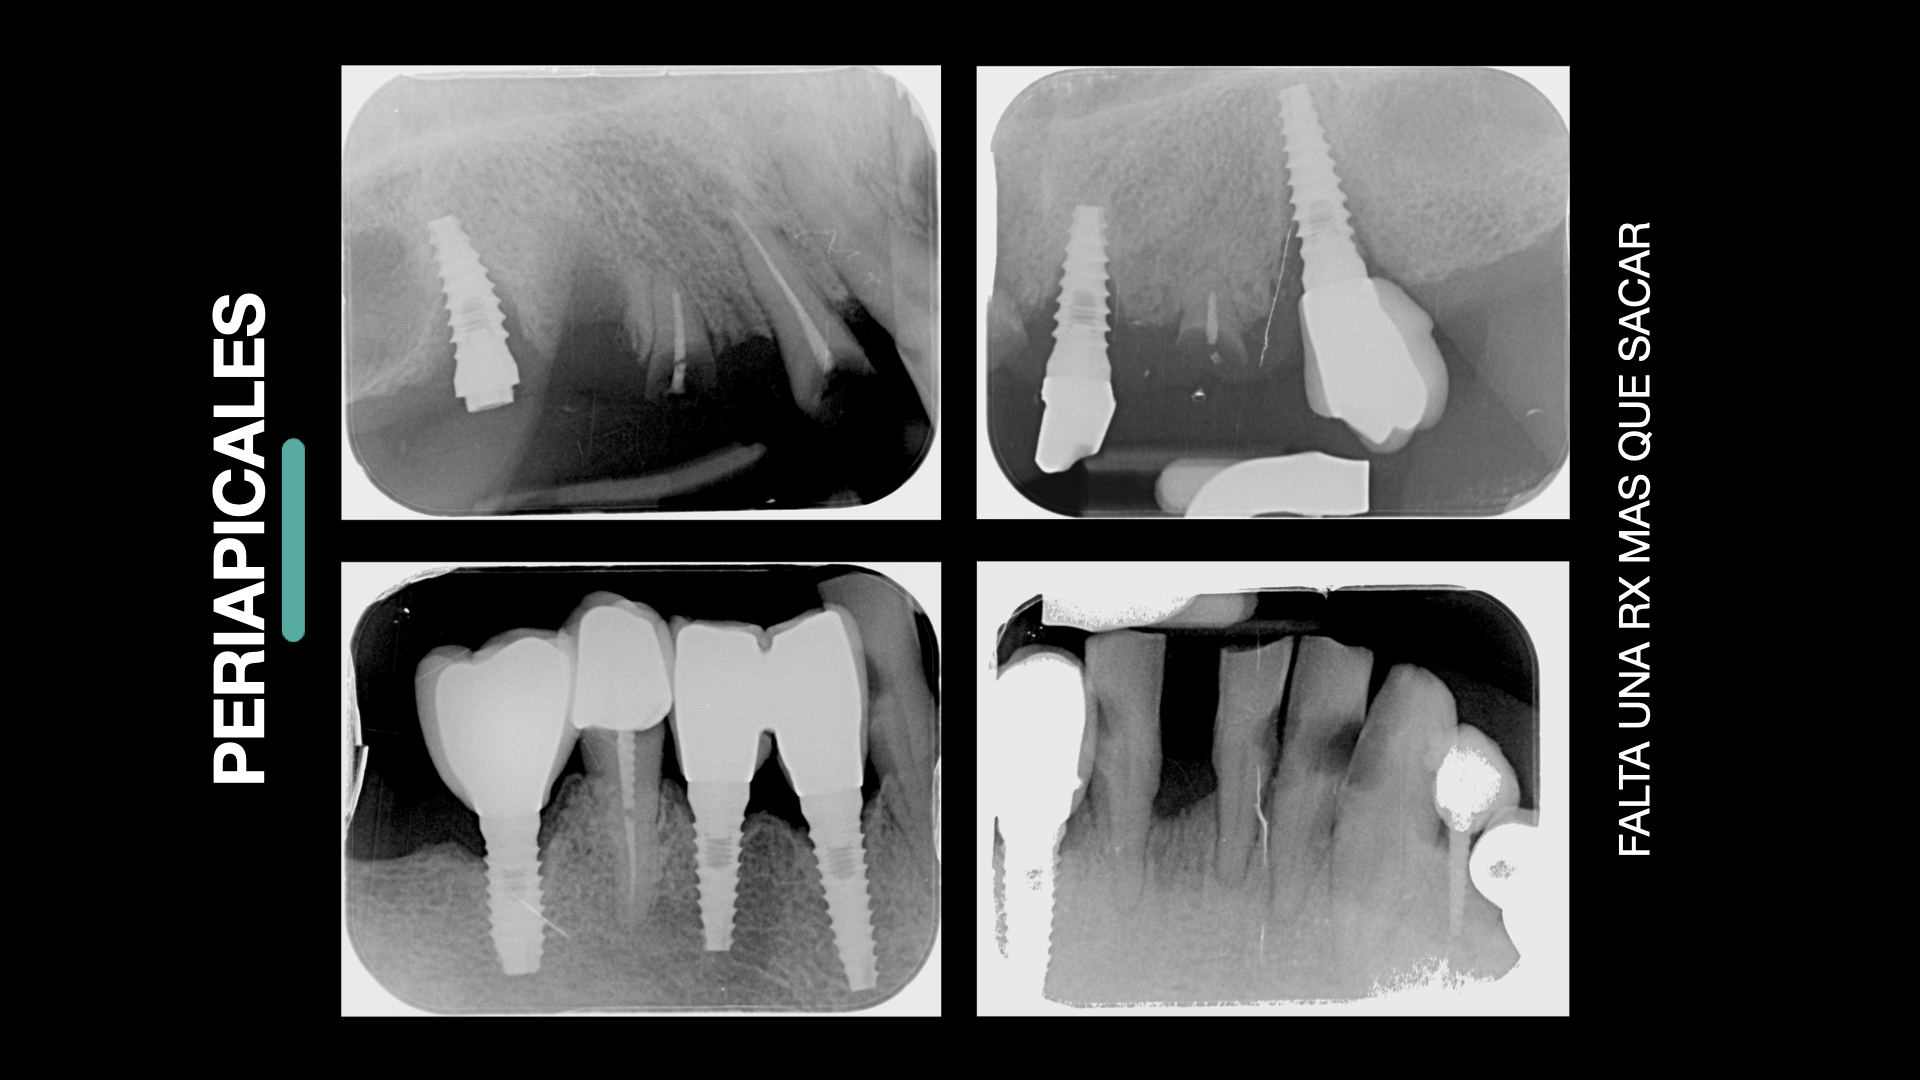

- Directo a implante

- Edéntulo total